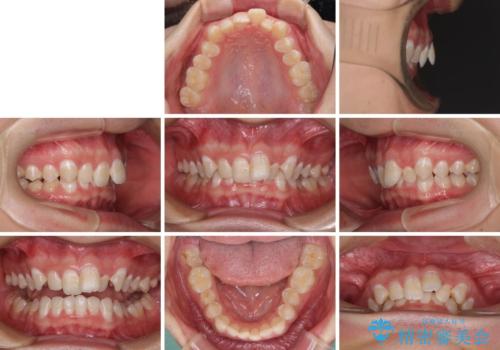

- 強い咬み合わせと前歯のデコボコを気にして来院された患者様です。

下顎前歯が全て隠れてしまうほどの深い咬合で、左右の奥歯は1歯対1歯で咬み合う状態でした。

前方に移動している上顎臼歯を補助装置にて遠心移動させることで1歯対2歯の臼歯咬合を目指し、同時に深い咬合を改善していくこととしました。